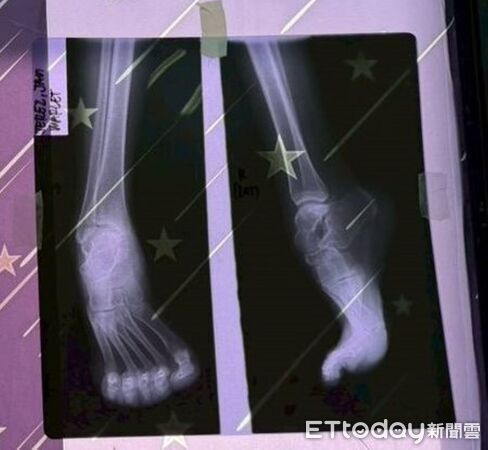

在本次義診行動中,最令醫療團隊掛心的,是一位患有先天足部畸形的少女。嘉基團隊早在 2025 年的行動中便與她相遇,當時因足部結構異常導致她行走維艱,甚至因外觀差異產生自卑感,影響學業與社交。醫療團隊返台後並未忘記這份託付,歷經一年的精密規劃,此次特別攜帶完整的醫療設備與專業團隊,在資源有限的環境下順利完成足部矯正手術。看著手術後明顯改善的足部外觀,團隊成員深感欣慰,這不僅是功能上的修復,更是讓少女重新找回自信、重返校園的新契機。